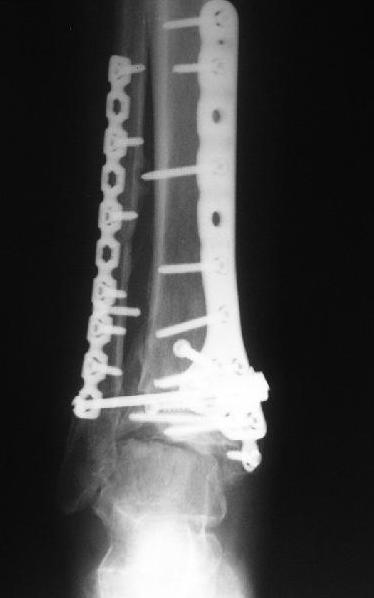

Dear коллеги, Обратилась женщина, 25 л. 8 мес. назад в одной из больниц сделан остеосинтез пилона. На сегодня ходит без дополнительной опоры, хромая на поврежденную ногу. Движения в голеностопном суставе еще есть. Снимки в приложении.

Вопрос - что делать? Замыкать сустав пациентка пока не настроена (наверно, получится настроить, если задаться такой целью). Нет ли смысла попытаться сделать какую-то восстановительную операцию? Допустим, получится устранить подвывих, восстановить межберцовые соотношения - это что-то хорошее надолго даст? Или упросто убрать "железо", и этим ограничиться, пока сама не придет за артродезом?

Есть ли здесь смысл пытаться организовать эндопротезирование? В смысле, доступные сейчас протезы применимы в этой ситуации?

A female, 25, 8 month ago operated elsewhere. To date walks without support with pain and limp. The ankle is mobile yet. Images attached. The question is what to do now? The patient is not very keen on ankle fusion (though likely could change her mind if necessary) Is it worth to try a reconstruction procedure and what kind? Maybe it allows to restore alignment and tibio-fibular relationship - will it provide painless limb for more or less significant time? Or just remove the hardware and leave her alone until she herself comes for fusion?

Are available total ankle implants suitable for the situation? If yes what one?